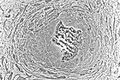

Osteoblasts (blue) rimming a bony spicule (pink - on diagonal of image). In this routinely fixed and decalcified (bone mineral removed) tissue, the osteoblasts have retracted and are separated from each other and from their underlying matrix. In living bone, the cells are linked by tight junctions and gap junctions, and integrated with underlying osteocytes and matrix H&E stain. | |

Hematoxylin and eosin staining (H&E) shows that the cytoplasm of active osteoblasts is slightly basophilic due to the substantial presence of rough endoplasmic reticulum. The active osteoblast produces substantial collagen type I. About 10% of the bone matrix is collagen with the balance mineral.[2] The osteoblast's nucleus is spherical and large. An active osteoblast is characterized morphologically by a prominent Golgi apparatus that appears histologically as a clear zone adjacent to the nucleus. The products of the cell are mostly for transport into the osteoid, the non-mineralized matrix. Active osteoblasts can be labeled by antibodies to Type-I collagen, or using naphthol phosphate and the diazonium dye fast blue to demonstrate alkaline phosphatase enzyme activity directly.

Light micrograph of decalcified (a process that removes the mineral) cancellous bone displaying osteoblasts actively synthesizing osteoid, containing two osteocytes.